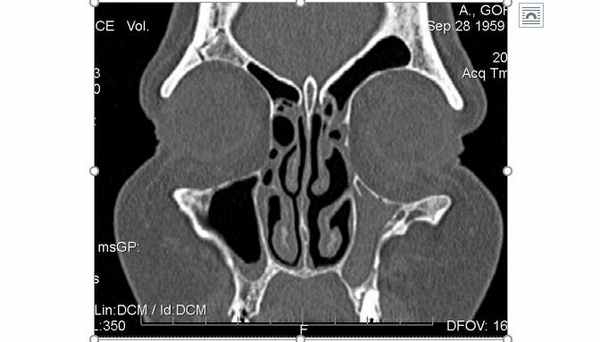

Рис.1. Серия фронтальных срезов конусно-лучевой компьютерной томографии (КЛКТ) у пациентки с синдромом «молчащего» синуса.

Рис.2. Серия аксиальных срезов конусно-лучевой компьютерной томографии (КЛКТ) у пациентки с синдромом «молчащего» синуса.

На КТ ОНП: тотальное затемнение правой верхнечелюстной пазухи, уменьшение её в размерах за счет втяжения костных стенок, опущение нижней стенки орбиты (2-я стадия ателектаза верхнечелюстной пазухи по классификации Kass).

Пациентка обратилась к ортодонту с проблемой вестибулярного положения клыка после чего была направлена на КТ. При расшифровке компьютерной томографии помимо основной проблемы был диагностирован синдром «молчащего синуса».